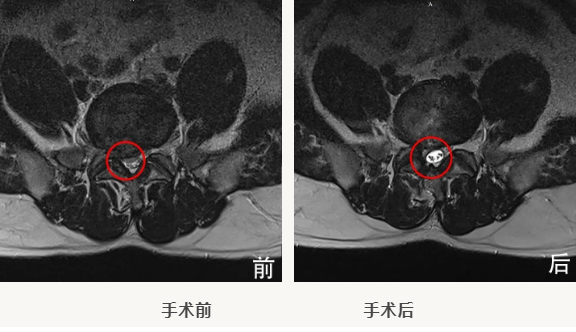

事情还要从今年八月份说起,孙先生是一位36岁的腰间盘突出患者,八月份因腰部疼痛、活动受限、行走困难,严重影响到日常生活,在跑遍各个医院进行理疗、自行贴敷膏药治疗无明显好转后,于北京燕化医院骨科就诊。经过一系列的CT、核磁排查后确诊为“腰椎间盘突出症”,核磁显示孙先生“L5/S1腰椎间盘右下侧脱出”,遂被收入骨科。

骨科团队仔细研讨病历后,于8月20日由主治医师杨宏宇牵头,并在北医三院专家的指导下为患者实施了 “脊柱内镜下椎间盘摘除”微创手术,手术顺利完成。术后在杨大夫以及骨科康复师的指导下孙先生两天左右便可戴围腰下地活动自如,跛行以及活动困难等生理活动基本恢复正常。